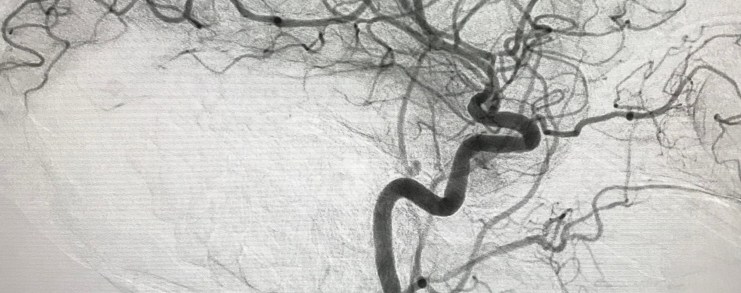

Large Artery Occlusion

See images from a stroke thrombectomy.